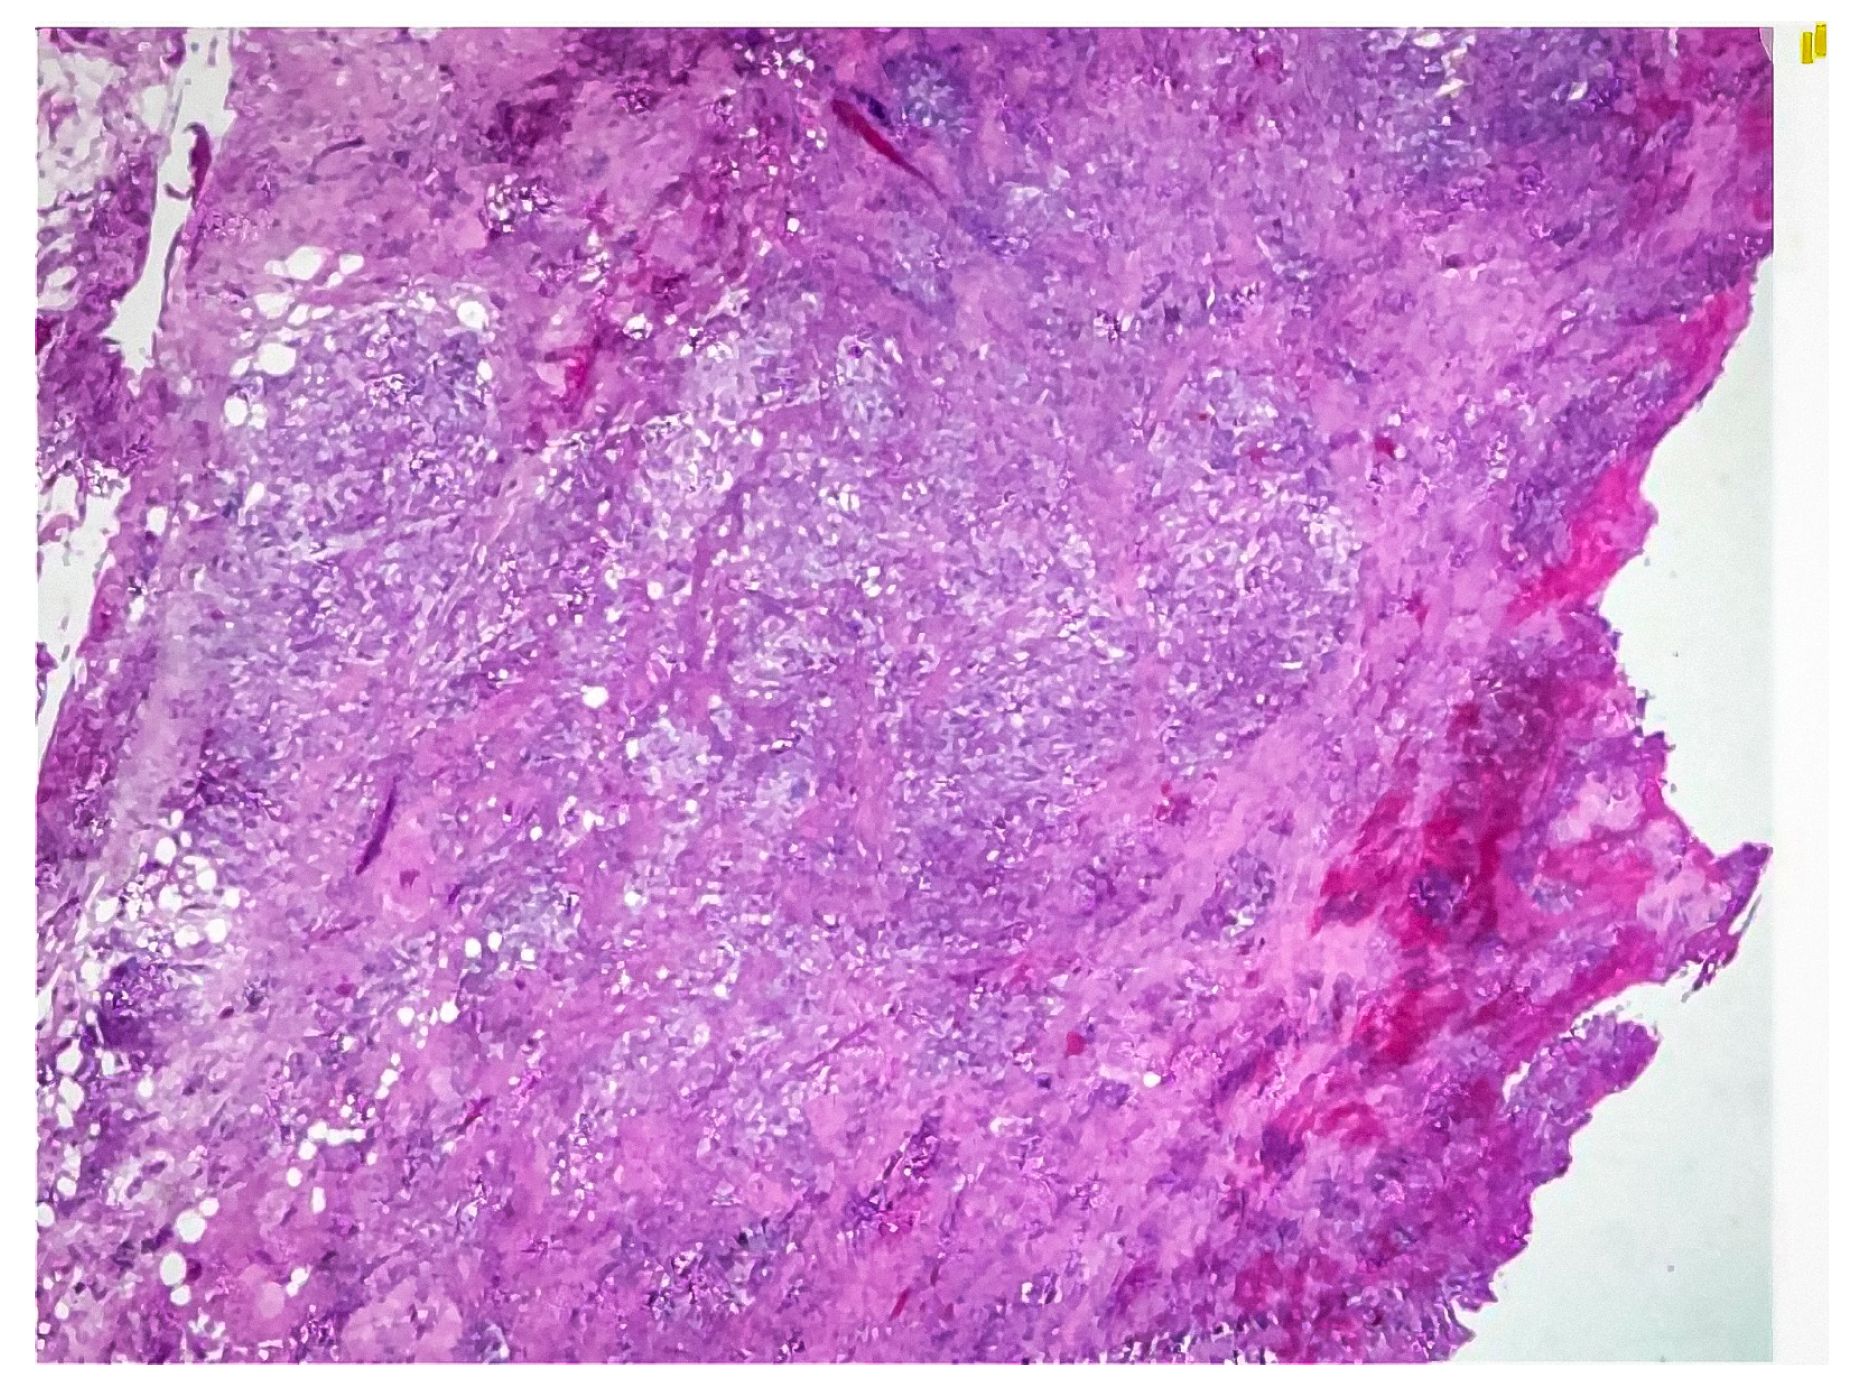

Figure 3.

Hematoxylin and eosin (H&E) stained sections showing dense inflammatory infiltrates, xanthoma cells, and fibrosis consistent with xanthogranulomatous cholecystitis.